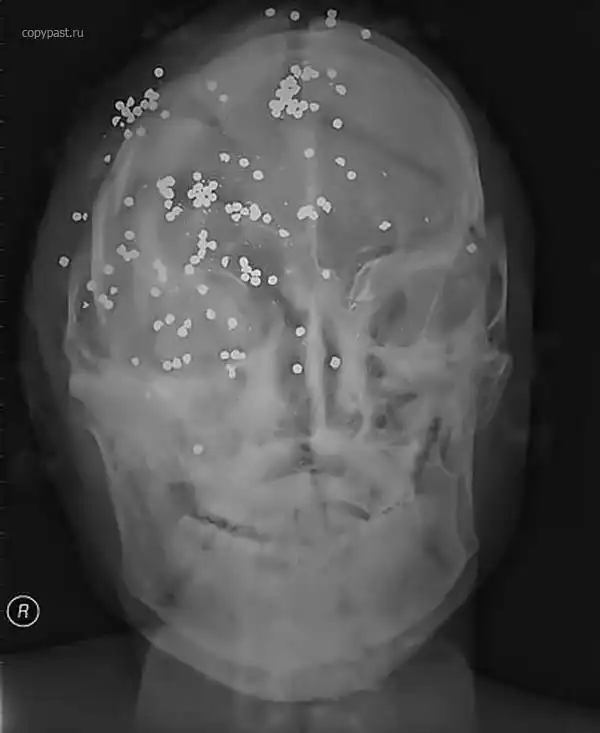

Убийство. Множественные выстрелы в голову

Ранения дробью в голову